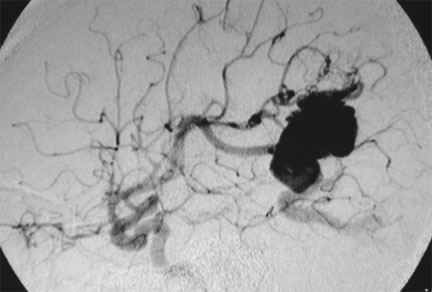

CASO 2 : Embolización combinada con Radiocirugía. Paciente con crisis convulsivas y trastorno del lenguaje. La angiografía demuestra voluminosa MAV localizada en plena área del lenguaje.

Angiografía antes de la embolización